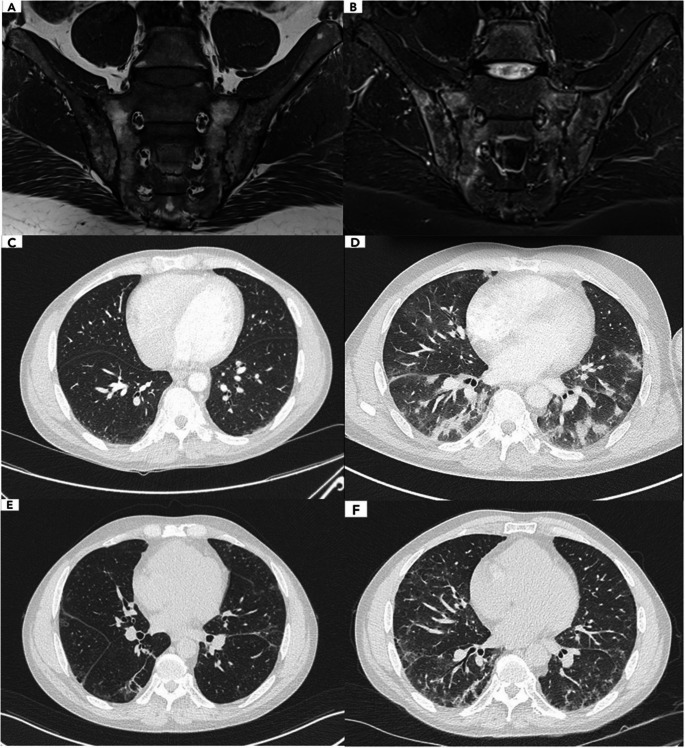

Fig. 1.

Sacroiliac MRI at diagnosis and chest CT scan evolution over time (Patient 1) (A) Sacroiliac MRI showing subchondral bone erosion and fatty conversion, reflecting chronic structural damage (T1). B Peripheral subchondral bone edema and anterior capsule infiltration, reflecting active inflammation (STIR). C Chest CT scan: before adalimumab introduction, showing no interstitial lung disease. D Eleven months after adalimumab introduction, showing diffuse interstitial pneumopathy with bilateral ground glass opacities. E Regression of the lung infiltrates, six months after oral methylprednisolone. F Worsening of the pulmonary lesions with progression to pulmonary fibrosis, one year after diagnosis

Our first patient is a 59-year-old HLA-B27 positive male, diagnosed with axial ankylosing spondylitis in 2016, in a context of cervical, lumbar and hip pain, with bilateral sacroiliitis, syndesmophytes and Romanus lesions on his initial MRI (Fig. 1A-B). He was well controlled with non-steroidal anti-inflammatory (NSAI) drugs until September 2019, when pain reoccurred; adalimumab 40 mg bimonthly was introduced. His chest-CT scan showed no special feature at that time (Fig. 1C).

In August 2020 he was hospitalized in pneumology for a suspected post-COVID pneumonia in a context of fatigue and growing dyspnea. Arterial blood gases at admission revealed hypoxemia with pH 7.45, PCO2 36 mmHg, PO2 63 mmHg, SaO2 92%. His biology showed total leucocytes of 9.240/uL, neutrophiles 6.480/uL, CRP 44 mg/L. Chest-CT scan revealed diffuse interstitial pneumopathy with bilateral ground glass opacities and an estimated 25–50% damage (Fig. 1D). Pulmonary artery thrombosis was ruled out. Cardiac assessment was unremarkable. SARS-CoV-2 serology was not tested, however all the SARS-CoV-2 PCR were negative during the hospitalization. Bronchoalveolar lavage disclosed 1300 leucocytes/uL with 54% of macrophages, 31% of lymphocytes, 13% of neutrophiles. Bacterial, mycologic and mycobacterial cultures came back negative. Invasive aspergillosis, Pneumocystis jirovecii, Chlamydia pneumoniae, Mycoplasma pneumoniae and other viral agents including SARS-CoV-2 were ruled out by PCR. Adalimumab was discontinued. Oral methylprednisolone 1 mg/kg was introduced. The patient evolved well and a reevaluation at six months showed a regression of the lung infiltrates (Fig. 1E). His pulmonary function tests (PFT) and arterial blood gases showed a positive evolution.

Looking back at the patient’s chest-CT history to determine the onset of his interstitial lung disease (ILD), we understood that it appeared in August 2020 when he was misdiagnosed as having COVID pneumonia. We concluded in an anti-PL7 ASyS with isolated lung involvement, which first manifestations occurred eleven months after adalimumab’s introduction. Interestingly, we were able to test ANA and anti-PL7 antibodies on the patient’s serum before adalimumab’s introduction: they were negative, showing a seroconversion during adalimumab treatment. Adalimumab was discontinued and a treatment with oral methylprednisolone 0.5 mg/kg was reintroduced. On his latest evaluation, his PFT showed no amelioration, with a progression to pulmonary fibrosis (Fig. 1F): rituximab was recently introduced.